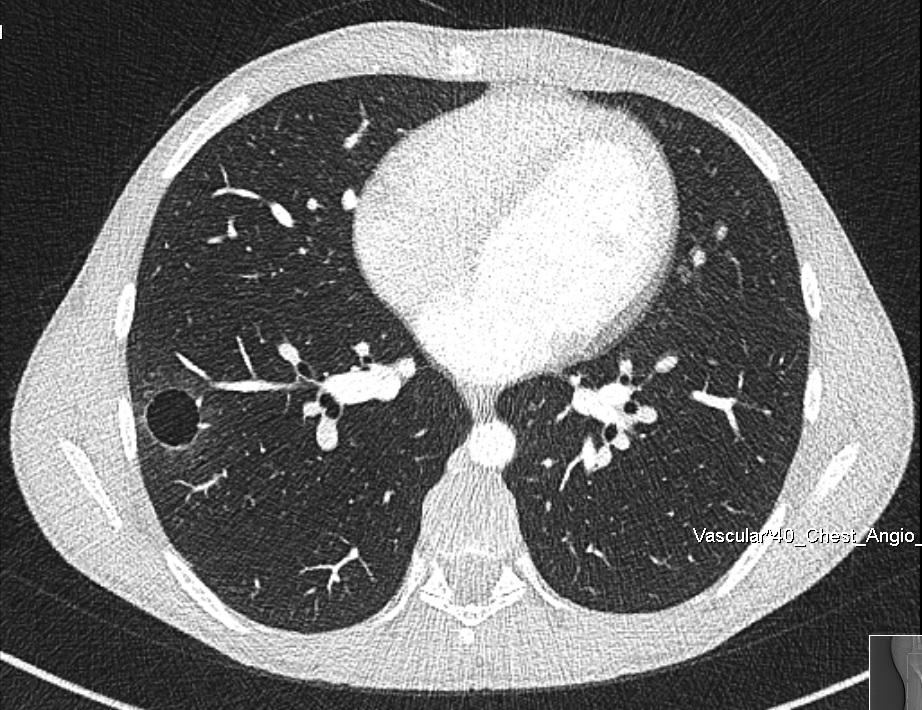

Figure 1. Chest CT scan.

Inflammatory myofibroblastic tumors (IMT) are relatively benign tumors that can occur in the lung, and also arise from different anatomical locations. In the lung, an IMT can be a solitary pulmonary nodule or a locally invasive lesion. The authors share the case of a 15-year-old male patient who presented with occasional hemoptysis. A chest computed tomography (CT) scan showed a cavitary lesion in the right lower lung lobe. A thoracoscopic segmental resection was performed, and the pathological result was an IMT. To the best of the authors’ knowledge, there are very limited reports of a lung IMT presenting as a cavitary lesion in the English literature.

Figure 2. Cavitary lesion in the right basomedial segment.

The authors report on the case of a 15-year-old male patient who presented with a two-year history of recurrent hemoptysis (about 60 ml), occurring once every three to four weeks. The hemoptysis was not related to physical activity or other respiratory symptoms and was self-limiting. The patient underwent a diagnostic fiber optic bronchoscopy that was inconclusive. A chest CT scan showed a cavitary lesion in the right basomedial segment of the right lower lobe of the lung. The patient's case was discussed in a multidisciplinary board meeting, and it was agreed that the right lower lobe lung lesion was the most probable cause of the patient's condition. The team planned a thoracoscopic uniportal video-assisted segmental resection of the right basomedial segment of the right lower lobe. The operative course was uneventful. The chest tube was removed three hours after the surgery, and the patient was discharged home on postoperative day one.